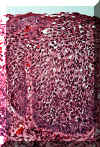

En algunos casos las anormalidades celulares son tan severas y la maduración del epitelio muy pobre, que el espesor entero del epitelio no hay diferencia entre la capa basal y la superficie. Cuando ocurre esto la lesión se designa carcinoma in situ. Todavía no hay infiltración en el tejido conjuntivo.

Con una resolución más alta de la imagen 66, puede ser algo difícil determinar qué lado es la basal y cual es la superficie. Las anormalidades celulares son obvias y la maduración es casi inexistente.